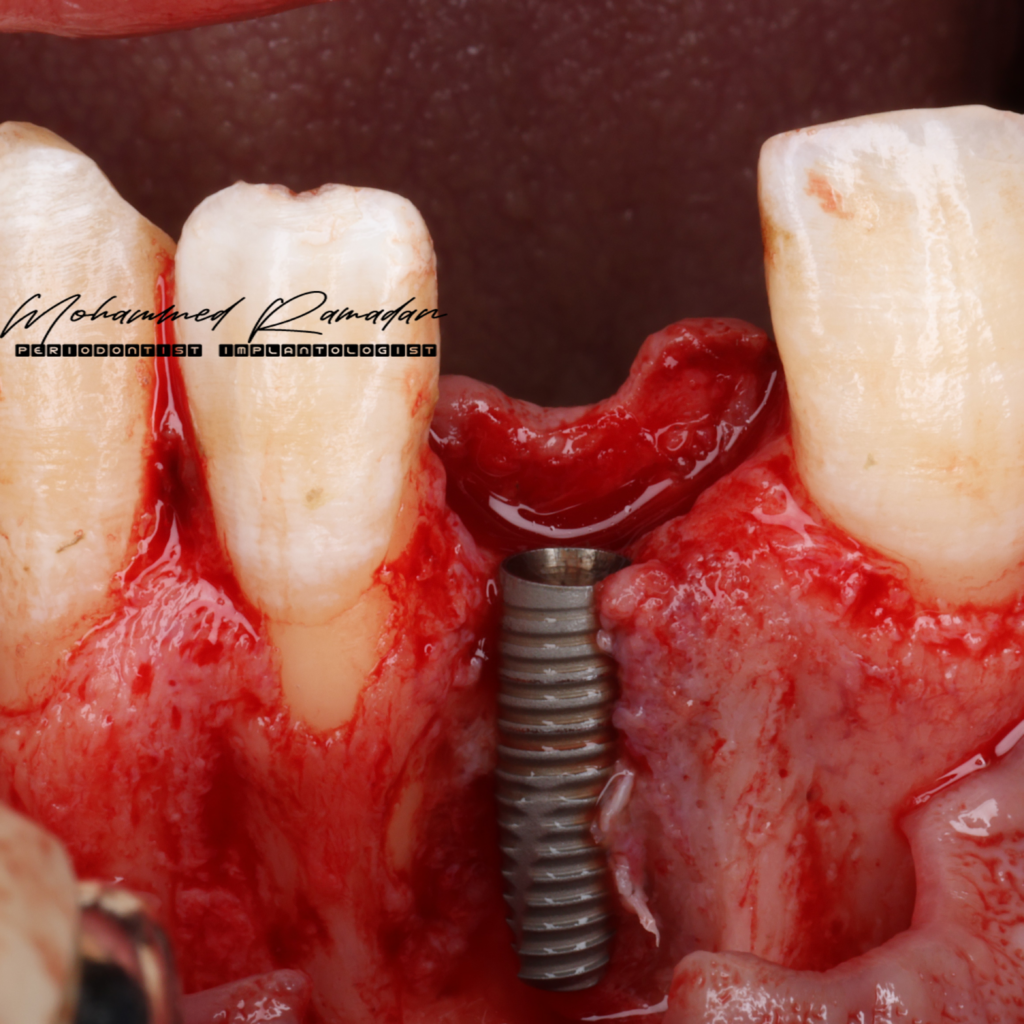

- Guided osteotomy preparation was performed, followed by fully guided implant insertion.

- Intraoperative Challenge: The implant was exposed from platform to apex. Despite this, adequate primary stability was achieved via palatal bone engagement.

- Possible Cause of Discrepancy: Poor CBCT quality with wide grayscale range, potentially misinterpreted as bone.

- Decision-Making: Although a staged approach was considered, patient time constraints necessitated continuation with simultaneous GBR using the sandwich technique.